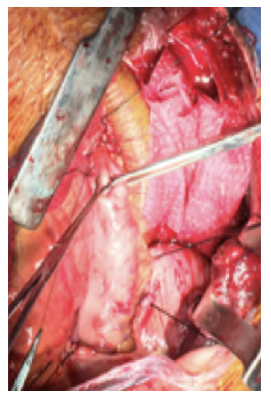

After a multidisciplinary discussion, a staged approach was decided. The first step aimed for oesophagus defunctionalization, by performing cervical oesophagus stapling, a drainage gastrostomy, and a feeding jejunostomy. After a two-week course of broad-spectrum antibiotics and antimycotics the patient underwent the definitive surgical treatment. A left lateral thoracotomy was performed, exposing the descending aorta and the oesophageal fistula (Figure 2). The stent graft was explanted (Figure 3), extensive debridement was followed by in situ reconstruction of the descending aorta with an aortic interposition of a silver and Triclosan impregnated Dacron graft (Figure 4), and lastly by esophagectomy (Figure 5), and eosophagogastrostomy (Figure 6). An intercostal muscle flap was used to fill the aortoesophageal space, to cover the graft and to take advantage of its neovascularization potential. The postoperative period elapsed without any major complications and the patient was discharged after 30 days. Antibiotic and antifungal drugs were administrated until discharge.

Figure 4 Descending thoracic aortic in situ interposition with silver and Triclosan impregnated Dacron graft.